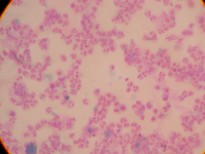

Figure 1: Electron microscope image of a small blood vessel (capillary) |

Figure 2: Breast carcinoma tumour cell undergoing mitosis (electron microscope image) |